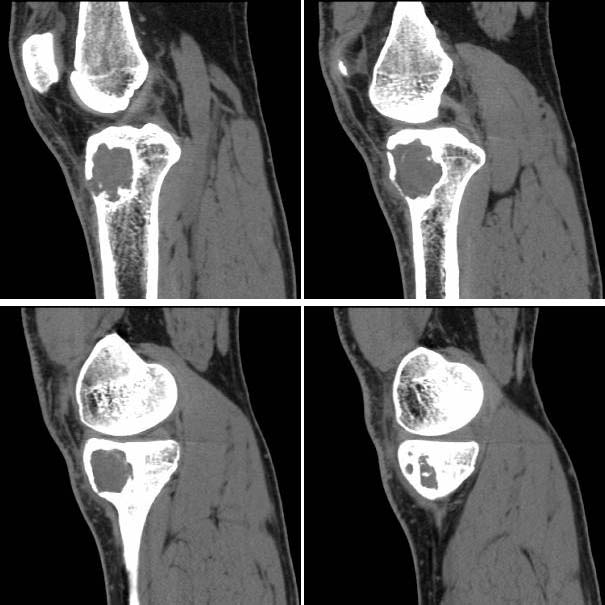

男,38岁,右膝下方剧烈运动后疼痛1年3个月,疼痛加重并局部隆起1个月。查体见轻度跛行,右胫骨近端前内侧轻度隆起,隆起部位压痛明显,皮温略有增高。右膝关节活动度基本正常,麦氏征、膝关节抽屉试验(-)。

胫骨近端、骨骺前内侧见局限性骨质破坏,边缘硬化明显,其间有少许残陈骨,边缘增生硬化,并可见嵴状突起,皮质部分断裂,无骨膜反应。

考虑:1、骨内腱鞘囊肿(邻关节囊肿);

征象:胫骨上干骺端偏心性类圆形骨质破坏,边缘硬化,可见病理性骨折,内有残留骨嵴。未见明显骨膜反应及软组织肿块。

诊断:动脉瘤样骨囊肿可能性大。